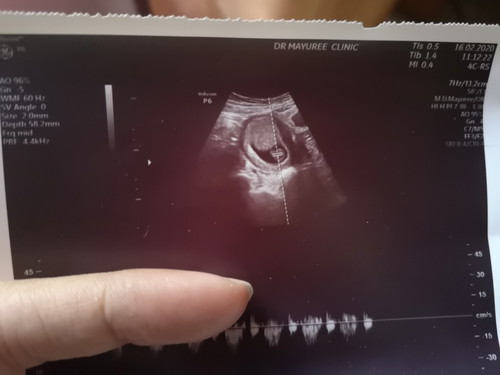

ใบซาวด์

สอบถามแม่ๆค่ะใบนี้บอกอะไรเกี่ยวกับเด็กบ้างคะ

หมอเขาจะบอกค่ะ ว่าลูกเราแข็งแรงมั๊ย อวัยวะครบรึป่าว ถ้าซาวช่วงแรกๆก็จะดูว่ามีน้องอยู่ในถุงครรภ์มั๊ย แล้วหมอก็จะให้ฟังเสียงหัวใจน้องด้วยค่ะ ว่าเต้นปกติมั๊ย